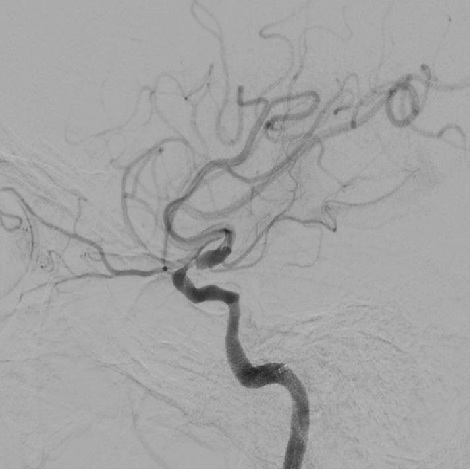

3、造影可见左侧颈内动脉前向血流恢复,M1段以远显影良好,眼动脉段可见重度狭窄,观察5分钟后,再次造影,眼动脉段以远血流速度明显下降,局部造影剂滞留,考虑与对侧前交通动脉的代偿供血形成湍流,有再次形成血栓的可能,遂对狭窄部位进行球囊扩张。

4、将微导丝+微导管小心通过狭窄部位,至于LMCA M1段,手推造影剂示真腔,撤出微导丝,送入长交换导丝撤出微导管,沿微导管送入赛诺2.0×10mm-152.8cm球囊至狭窄处,7atm充盈球囊及回抽,造影见狭窄较前改善,残余狭窄10%,远端血流速度改善,观察10分钟后造影见远端血流无明显变化。